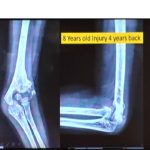

Courtesy: Saqib Rehman MD, Associate Professor, Director of Orthopaedic Trauma, Temple University, Philadephia, Pennsylvania, USA

From the 8th Annual Philadelphia Orthopaedic Trauma Symposium, June 10, 2016 at Lewis Katz School of Medicine at Temple University